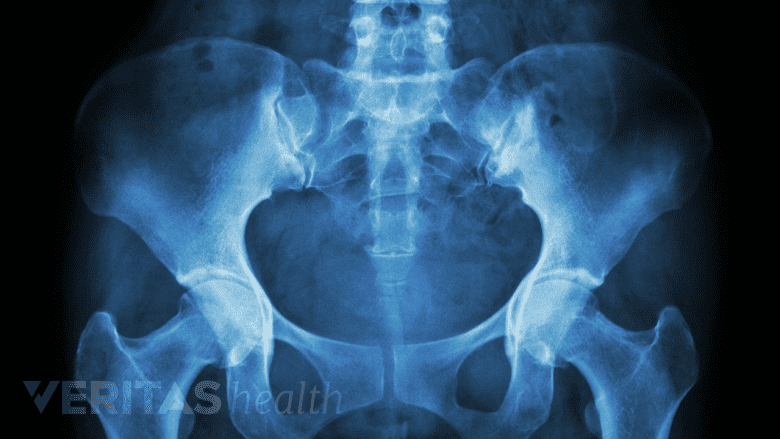

• X-rays of the spine can show bone spur formation and signs of spinal degeneration. X-rays can also help the physician determine if additional medical imaging, such as a CT or MRI scan, is needed.